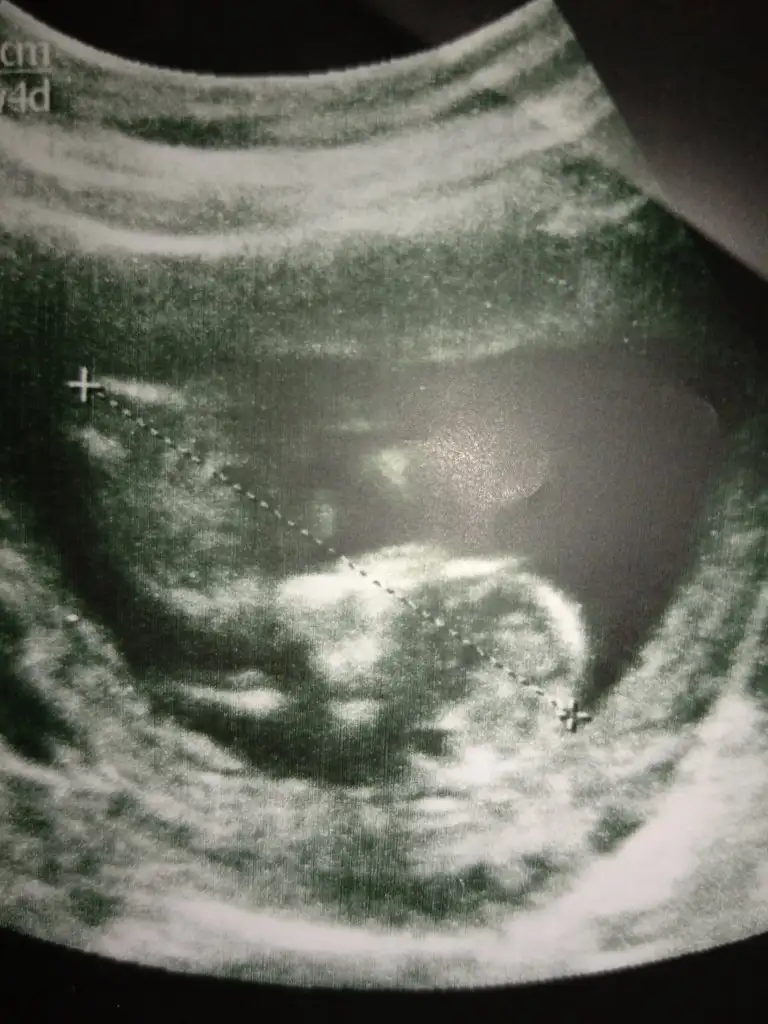

Daha önceki ultrason fotolarından anlayabilirmisiniz yollasam buradan yok göstermiyor bir türlüKaç haftalık sanki erkek gibi geldi başka usg varsa paylaşın az yan pozisyonda minnoş

Kizz :)Bir başka ultrason istemiştiniz bunlar var elimde bacaklarini bağlamışti öylece duruyorduheyecanla yorumunuzu bekliyorumm Ikra meyra

Çok net değil usg ler sanki kız gibi ama emin değilim ☺Bunlar dan belli olurmu acaba biraz ultrason fotolarından şansımız yok ama kısmet artık☺